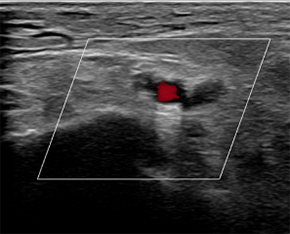

I scanned her with my Clarius L15 HD. The ultrasound scan revealed two boney fragments arising from the calcaneocuboid joint, with soft tissue oedema and hyperaemia of the periosteum seen with power Doppler. The clinical ultrasound findings were consistent with an avulsion fracture of the superior dorsal cuboid associated with bifurcate ligament injury, later confirmed on MRI.